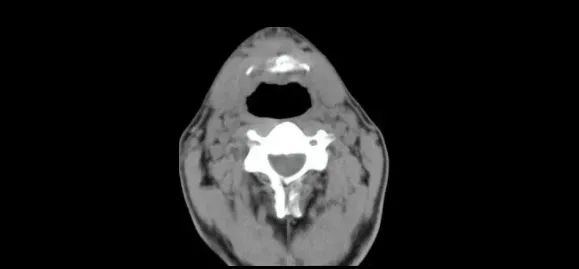

后来又查出来了咽炎,甚至因为咽炎,舌骨出现了一个3厘米左右的囊肿,所有的医院检查完后,给到的调理方案都是手术。

顶着全家人的压力,小周女儿用了两周的中药,两周过后再一查,囊肿小了足足一公分!